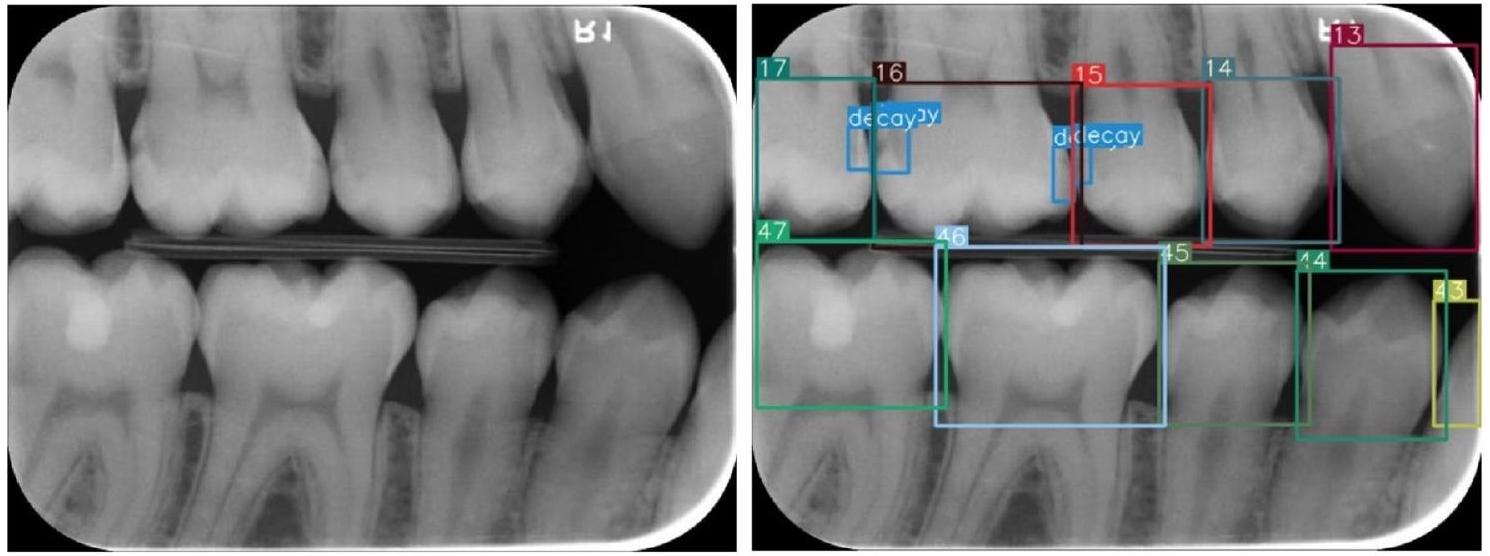

Image evaluation and data labeling

to Federation Dentaire International (FDI) tooth notation system (16-17-18-26-27-28-36-37-38-46-47-48 (molars), 14-15-24-25-34-35-44-45 (premolars) and 13-23-33-43 (canines)). Also, caries lesions labeled as decay in digital bitewing images. While in the data labeling procedure,

annotators reviewed the bitewing images at the same time and as a result of the agreement, labeling was processed (Fig. 3).